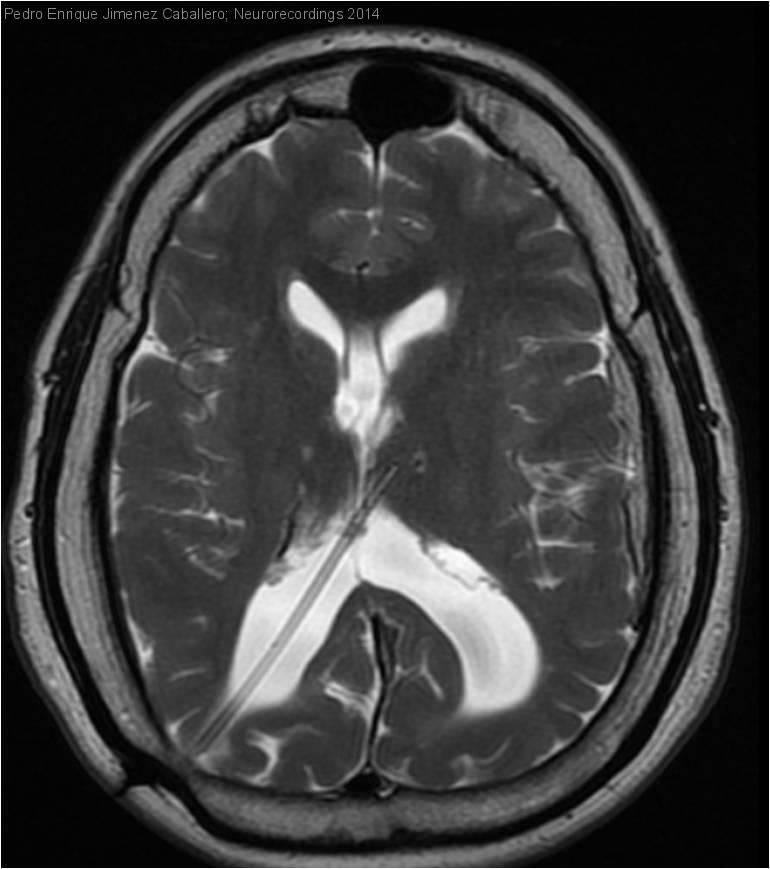

Hombre | 27 años

Diagnóstico final: Epilepsia con crisis parciales complejas frontales secundarias a Toxoplasmosis congénita

Varón de 27 años con antecedentes de Retraso Psicomotor severo secundario a Toxoplasmosis congénita y valvula de derivación ventriculoperitoneal por hidrocefalea obstructiva. Presenta a los 26 años episodios de pérdida de conciencia con desconexión del...